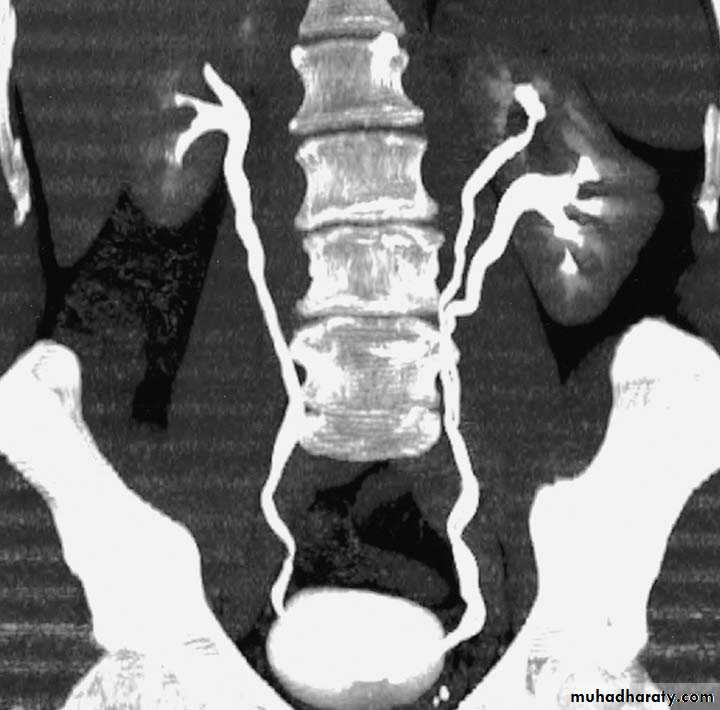

Postcaval (Retrocaval) ureter (Preureteral Vena Cava )

The right ureter pass behind the inferior vena cava

This might causes obstruction

Vascular abnormality

Incidence: about 1 in 1500Although it is congenital, most patients present at 3rd or 4th decade.

Diagnosis: IVU

Treatment:

surgical correction involves ureteral division, with relocation and ureteroureteral or ureteropelvic reanastomosis,

usually with excision or bypass of the retrocaval segment, which can

be aperistaltic